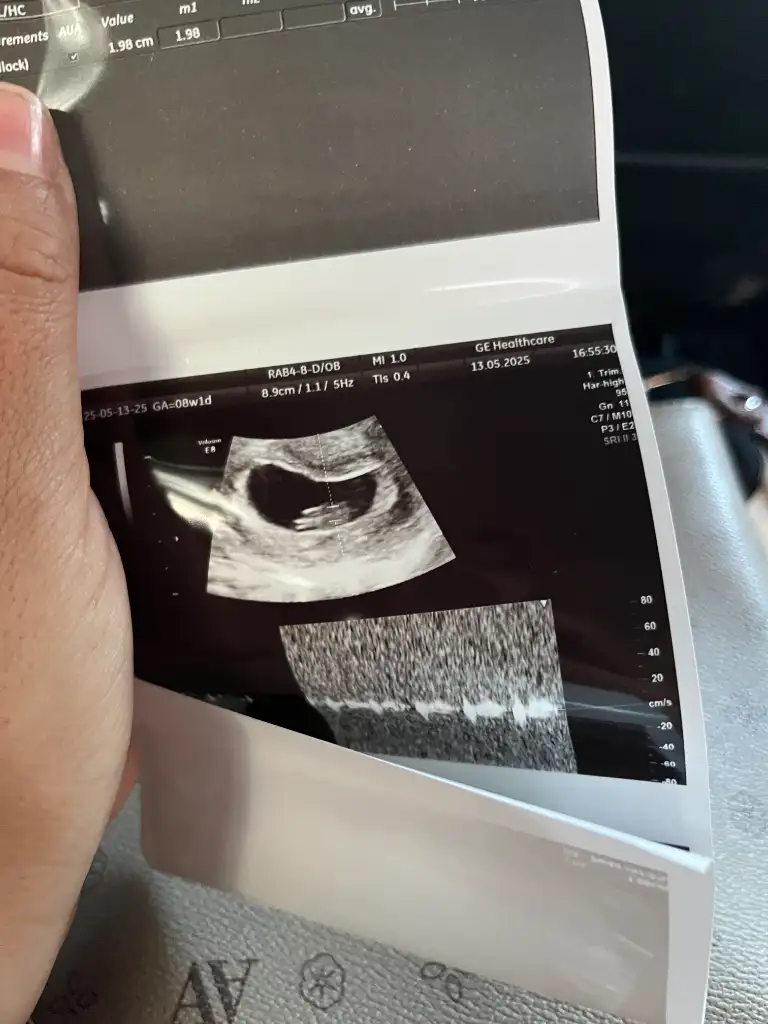

7+2 de ki ultrason da kalp atışı duydunuz mu ? Benim yarın kontrolüm var tam 7 haftalık duyar mıyız acaba kalp atışınıMerhaba 6+3 haftalık hamileyim. Rabbim isteyen herkese nasip etsin inşallah. İlk çocuğumuz elbette her şeyden önce sağlıkla gelsin

Ama ister istemez cinsiyetini merak etmeye başladık. Kese, teoriler vs. ye göre cinsiyet tahmini yapabilir misiniz

(Karından görüntüdür)

Not: mavili fotoğraf günceldir. 7+2 haftadan, karından